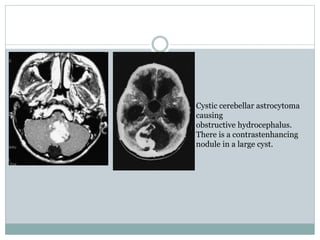

Cystic cerebellar astrocytoma

causing

obstructive hydrocephalus.

There is a contrastenhancing

nodule in a large cyst.